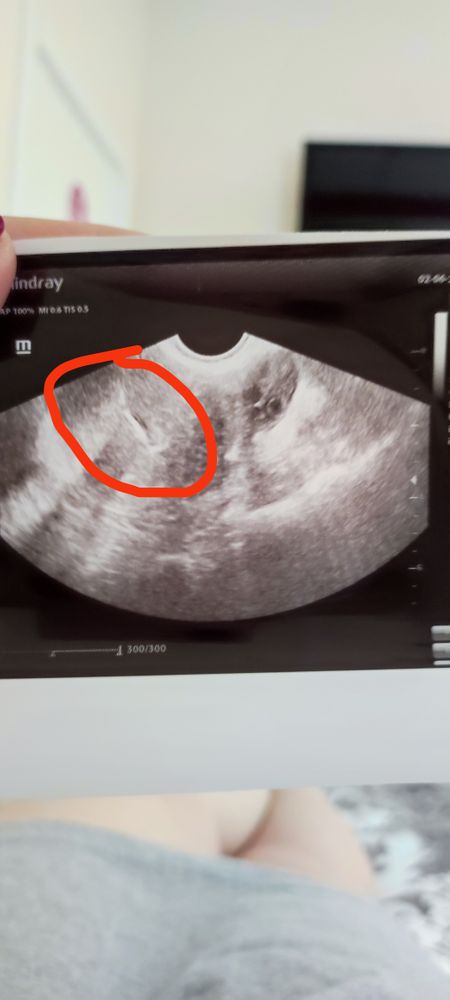

Малыш с нами

Крио ЕЦ Эко без гистероскопии